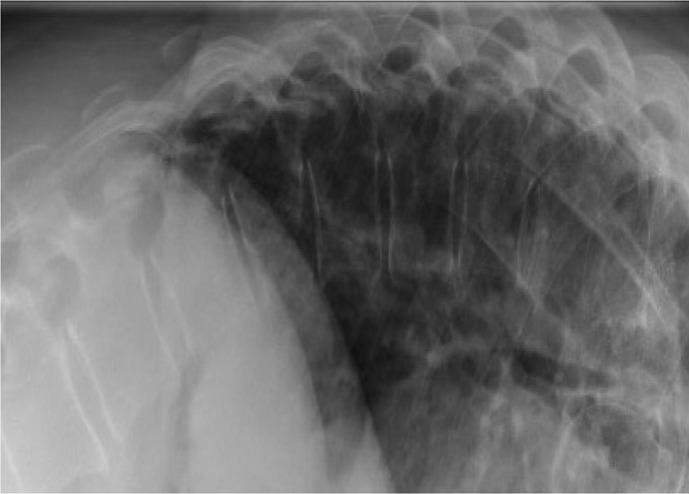

Case presentation: A 56-year-old female with presentation of acute on chronic mechanical low back pain was found to have multiple lytic lesions throughout the thoracolumbar spine arising from GIST metastases. Magnetic resonance imaging of the thoracic spine revealed a dorsal epidural enhancing mass spanning the T6-T8 levels with associated spinal cord compression and spinal cord signal change. The patient underwent urgent surgical decompression and resection of epidural tumor through T5-T8 decompressive laminectomy. Postoperatively, the patient initially did well with improvement in bilateral lower extremity sensation and bladder function. The patient passed away while at home due to undetermined causes 6 weeks postoperatively.